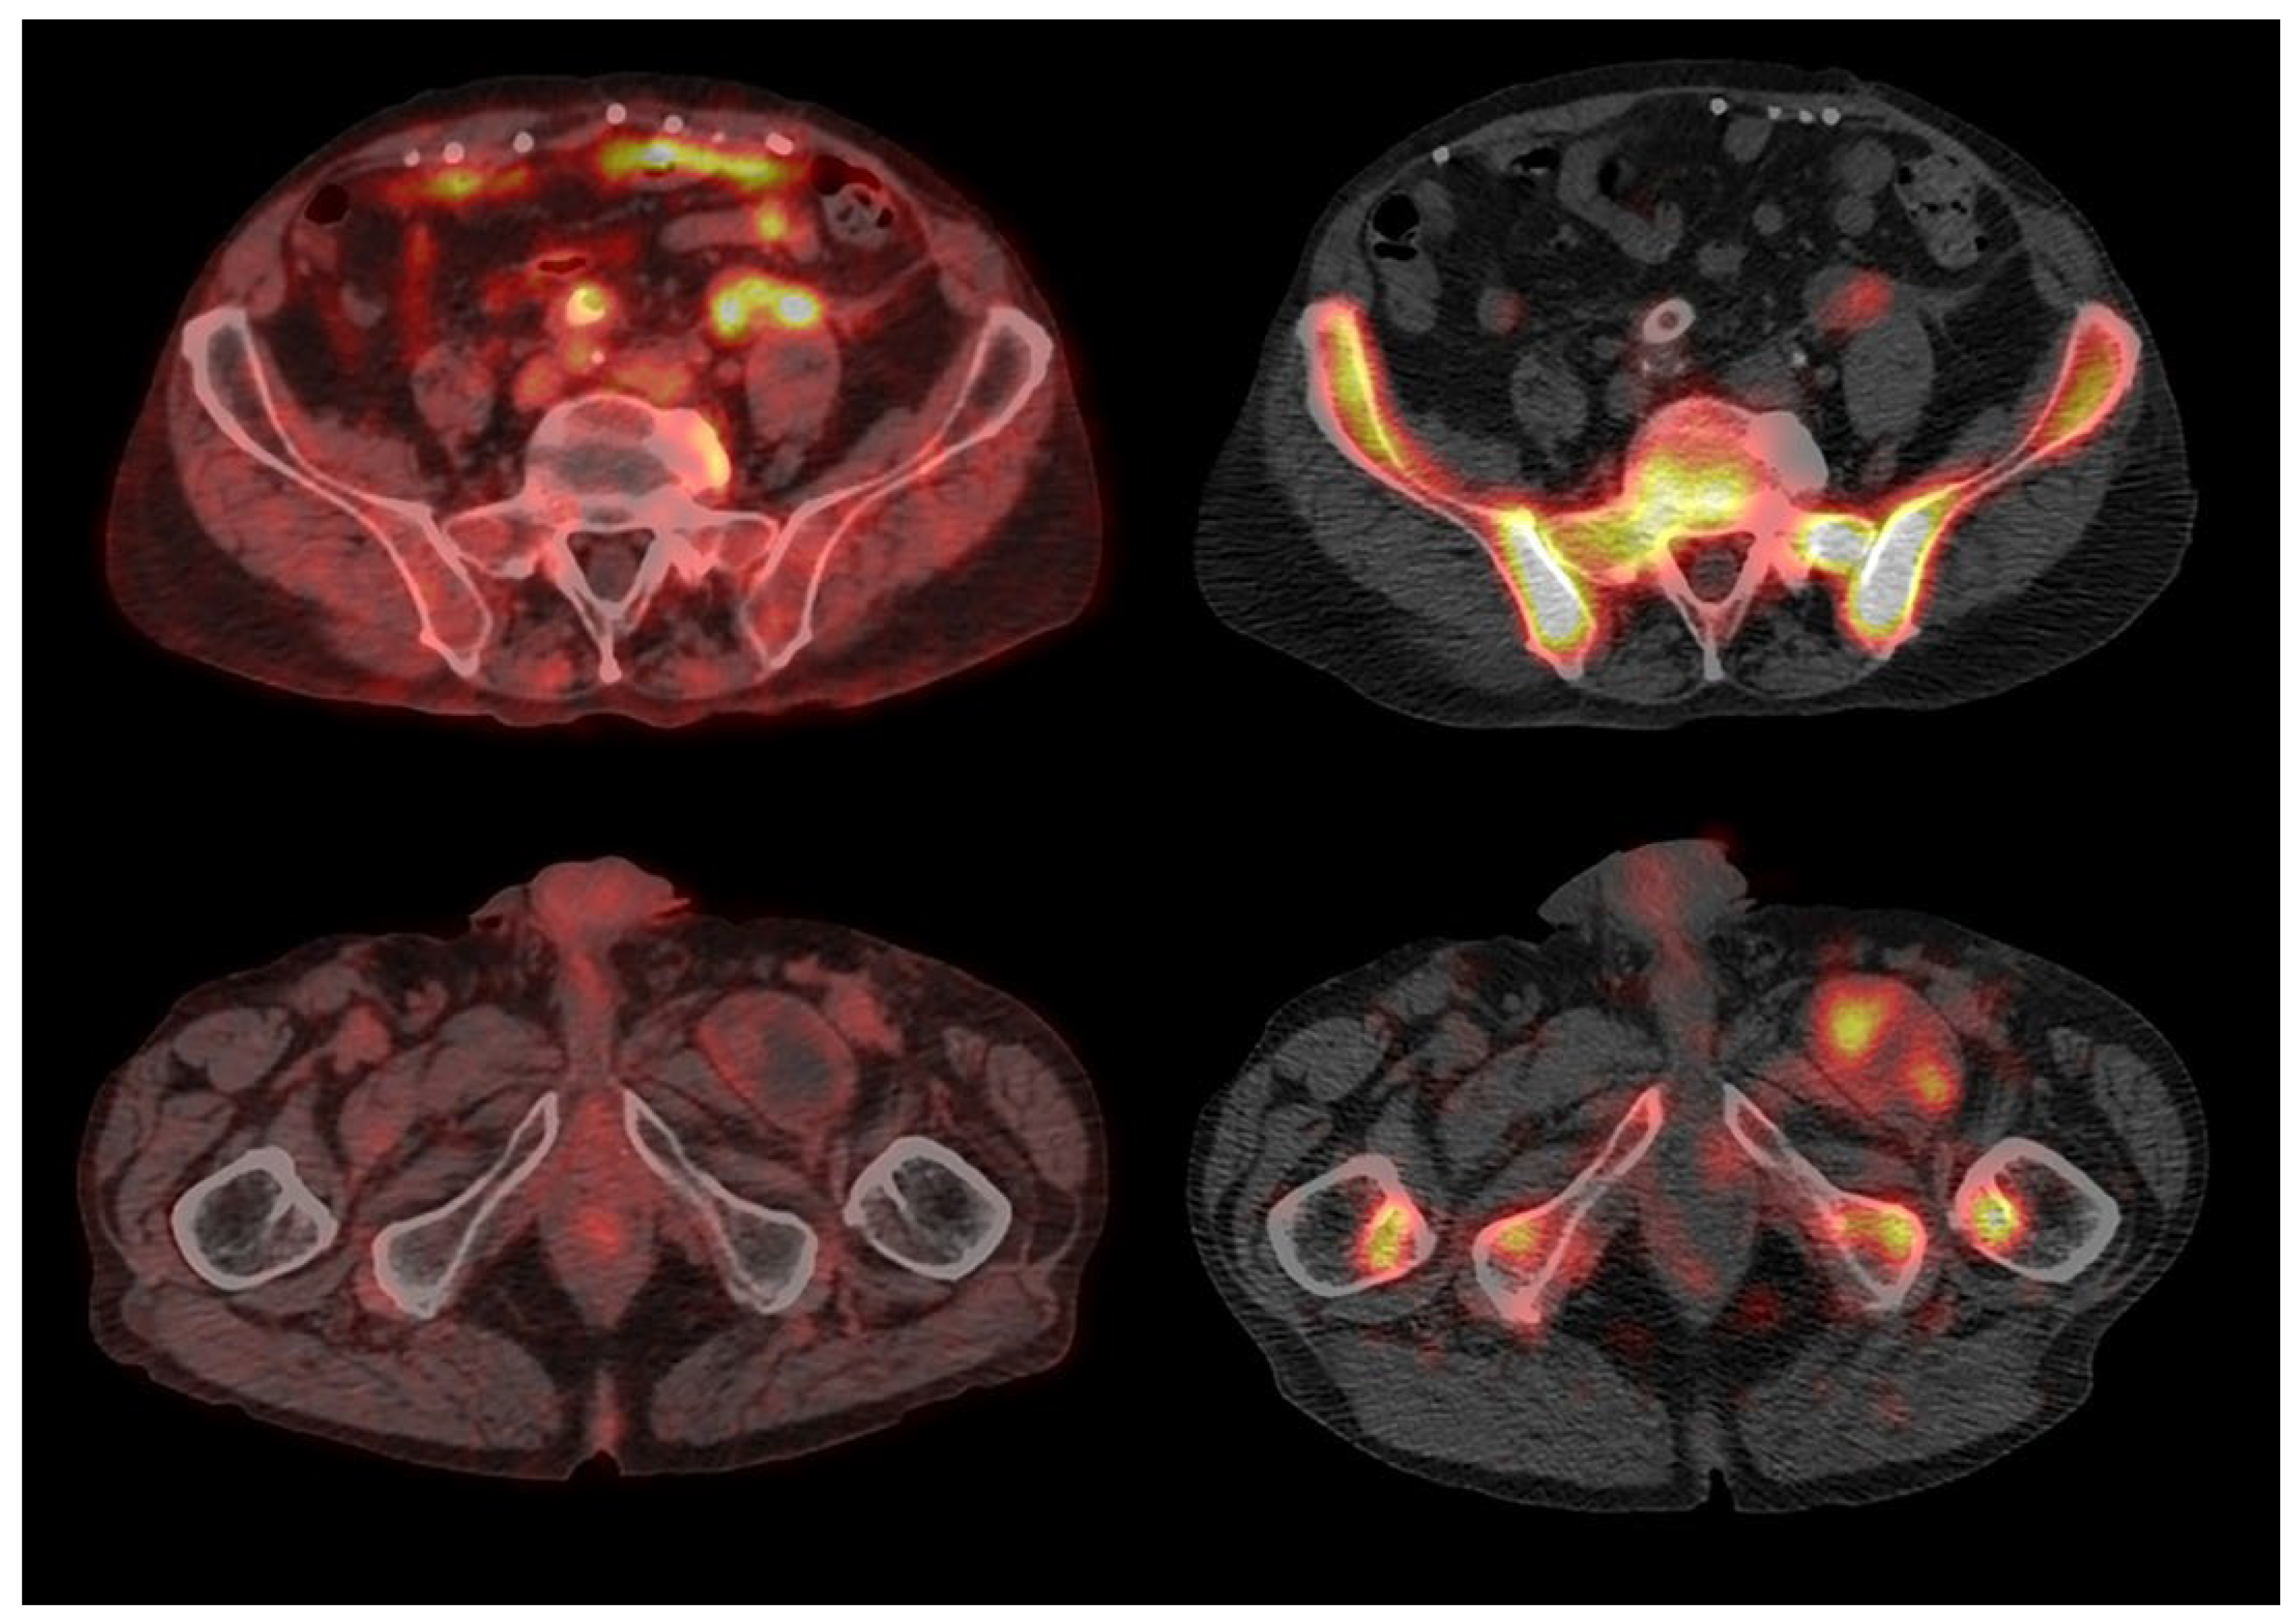

3. Results